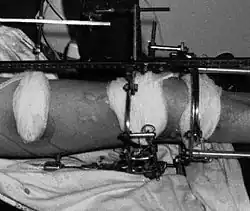

Конструкция аппарата и его наложение

Процедура лечения открытого перелома большой и малой берцовой костей аппаратом Илизарова. Фотографии и рентгенограммы одного и того же пациента в течение курса лечения. Снимки 2 — 6 сделаны через четыре недели после перелома (две недели после наложения аппарата).

Рентгенограмма перелома и первоначальный внешний фиксатор, наложенный в течение 24 часов после поступления в больницу. Вид аппарата Илизарова спереди и слева (перелом чуть выше черного металлического кольца).

Вид аппарата Илизарова спереди и слева (перелом чуть выше черного металлического кольца). Вид сверху. Пациент лежит на животе

Вид сверху. Пациент лежит на животе Фиксация спиц к кольцу